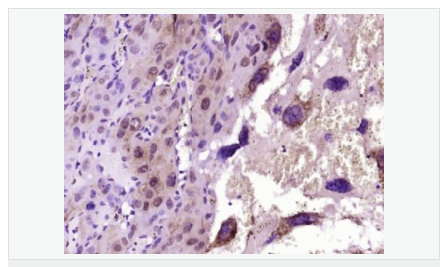

| 產品應用 | WB=1:500-2000 IHC-P=1:100-500 IHC-F=1:100-500 Flow-Cyt=1ug/Test ICC=1:100-500 IF=1:100-500 (石蠟切片需做抗原修復) not yet tested in other applications. optimal dilutions/concentrations should be determined by the end user. |

| 細胞定位 | 細胞核 細胞漿 細胞膜 線粒體 |